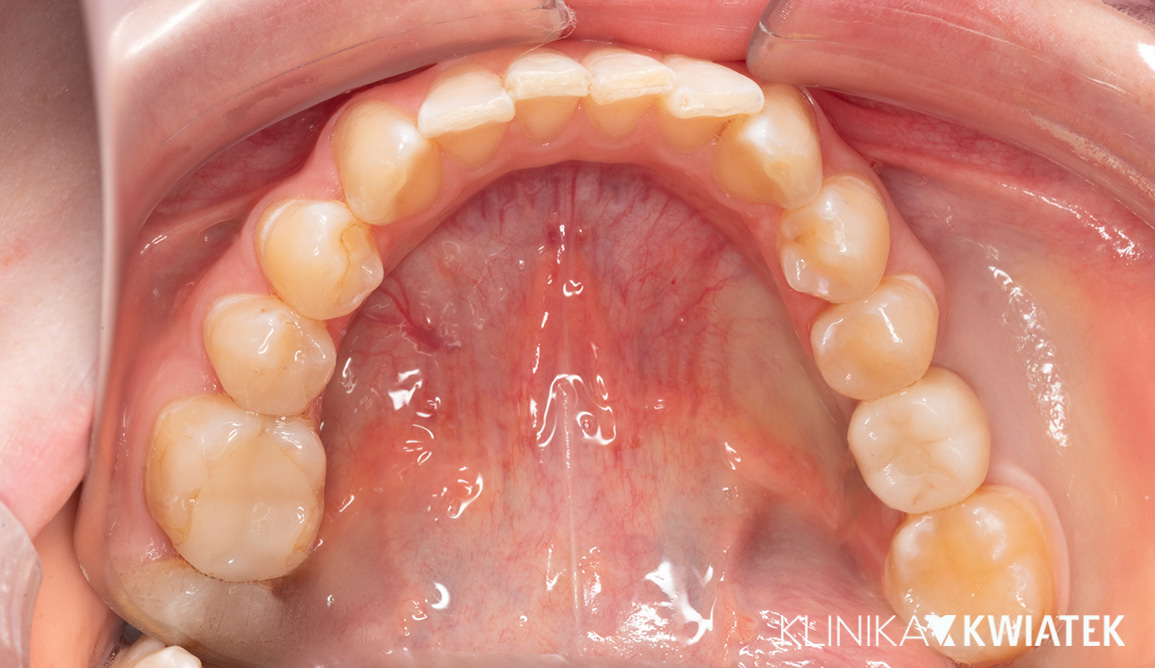

PRZED

PO

Pacjentka zgłosiła się z wadą zgryzu, licznymi ubytkami i utraconymi zębami trzonowymi, co powodowało trudności w żuciu i estetyczne niezadowolenie. Leczenie obejmowało ekstrakcje, ortodoncję, implantację oraz kompleksową rekonstrukcję protetyczną. Po kilkunastu miesiącach terapii Pacjentka odzyskała pełną funkcję zgryzu i piękny, harmonijny uśmiech.